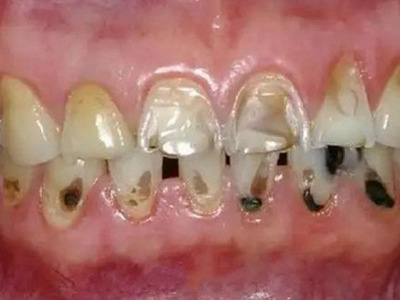

牙齿

缺损

酸蚀症牙齿缺损严重有黑斑图

酸蚀症严重时会使牙齿出现大面积缺损,有三颗下牙损毁严重,露出不整齐的牙骨质边缘,几乎仅余留牙根。缺损处有黑斑,局部呈黄褐色,需积极就医进行牙齿修复。